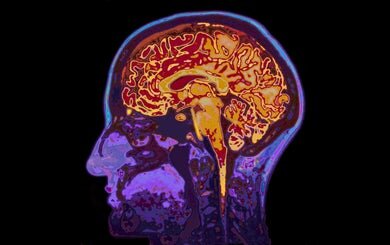

Вспоминания о похищении, когда вы были ребенком (в возрасте до трех лет) являются ложными почти по определению. Левая нижняя префронтальная доля не развита у детей, но необходима для долгосрочной памяти. Кодирование информации, необходимое для классификации и запоминания таких событий не может происходить в мозге ребенка.